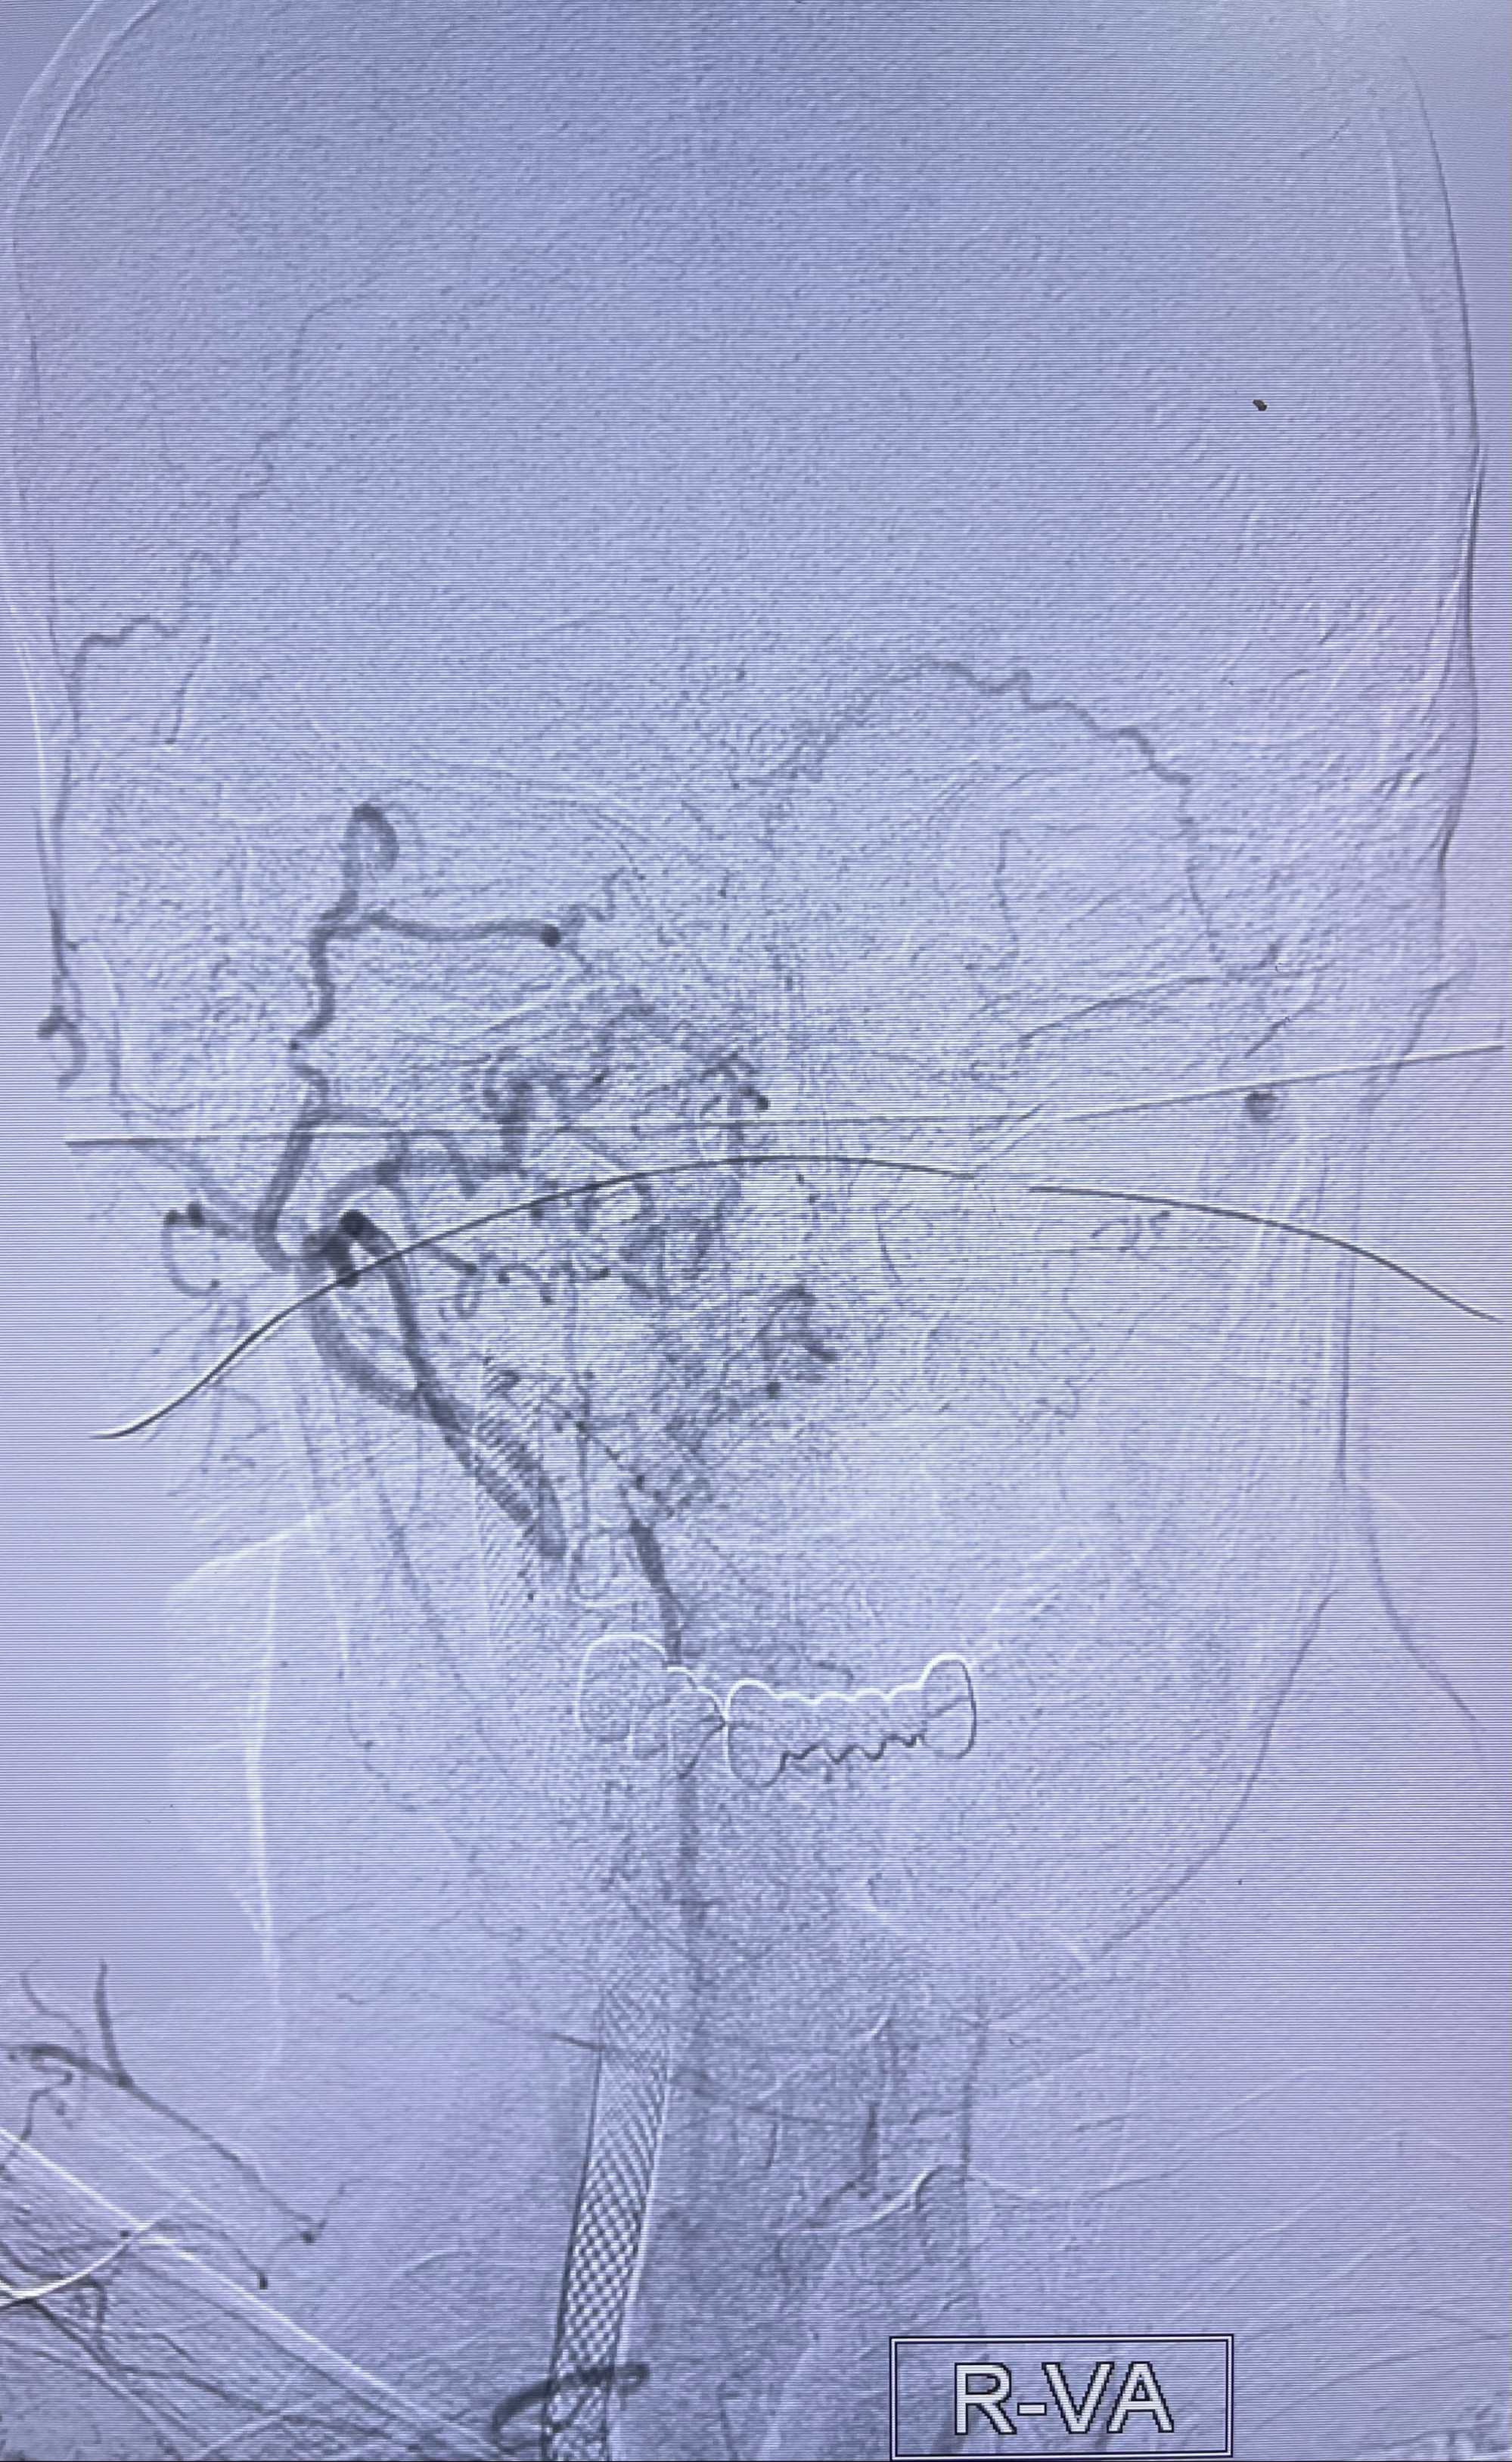

2023-07-10DSA:右侧颈内动脉岩骨段夹层伴中偏重度狭窄改变,左侧颈总动脉闭塞、右侧颈外动脉由右侧肋颈干甲颈干吻合代偿

右侧椎动脉可见吻合代偿右侧颈外动脉

左侧颈总动脉起始段至分叉部闭塞,起始部呈现子弹头样改变

左侧椎动脉可见代偿显示左侧前循环